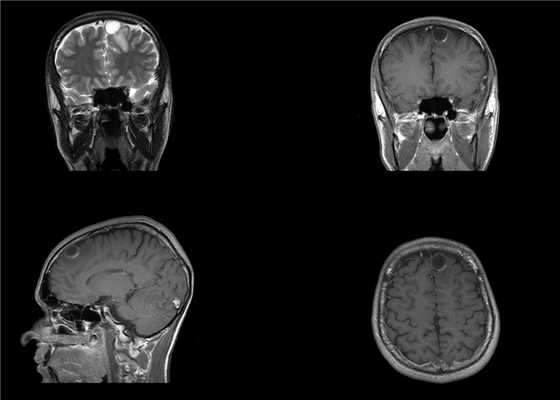

Пациентка 32 лет в течение месяца отмечает появления головной боли, сопровождающейся тошнотой и головокружением. Консультирована неврологом, направлена на МРТ, при которой выявлена внутримозговая опухоль правой заднелобной области, накапливающая контрастное вещество, с выраженным перифокальным отеком.

Пациентке проведена операция - микрохирургическое удаление опухоли правой лобной доли с использованием интраоперационного нейрофизиологического мониторинга.

Гистологический диагноз - морфологическая картина и иммунофенотип в большей степени соответствуют анапластической плеоморфной ксантоастроцитоме, WHO Grade III.

Молекулярно-генетическое исследование мутационного статуса методом ПЦР в режиме реального времени мутации гена BRAF V600E не выявлено.

При контрольной СКТ данных за остатки опухоли/послеоперационные осложнения не получено.

В послеоперационном периоде отмечается появление легкой асимметрии лица за счет левой его половины, практически полностью регрессировавшее к моменту выписки из стационара на 6 сутки.

При контрольной МРТ с контрастным усилением через 2 месяца данных за остатки опухолевой ткани не получено.